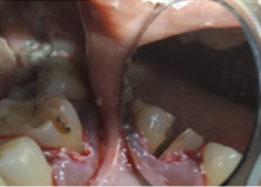

Hemisectomy

Post-OP Clinical View